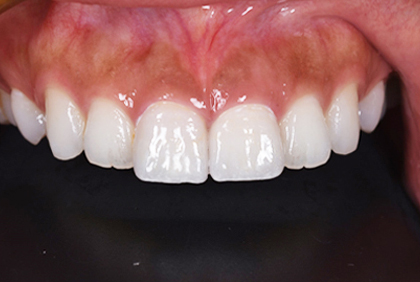

セラミックセット

最終的なジルコニアボンドクラウンをセットしました。すきっ歯がまずなくなりました。また、長かった歯が短くなりましたので本人の希望に沿うことができました。